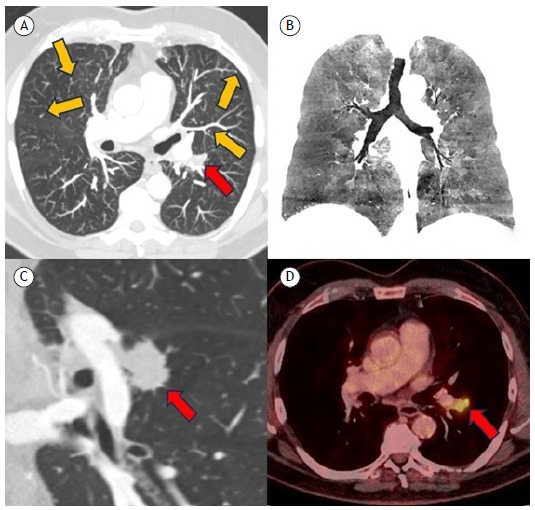

Diffuse idiopathic pulmonary neuroendocrine cell hyperplasia in a male patient associated with pulmonary adenocarcinoma.